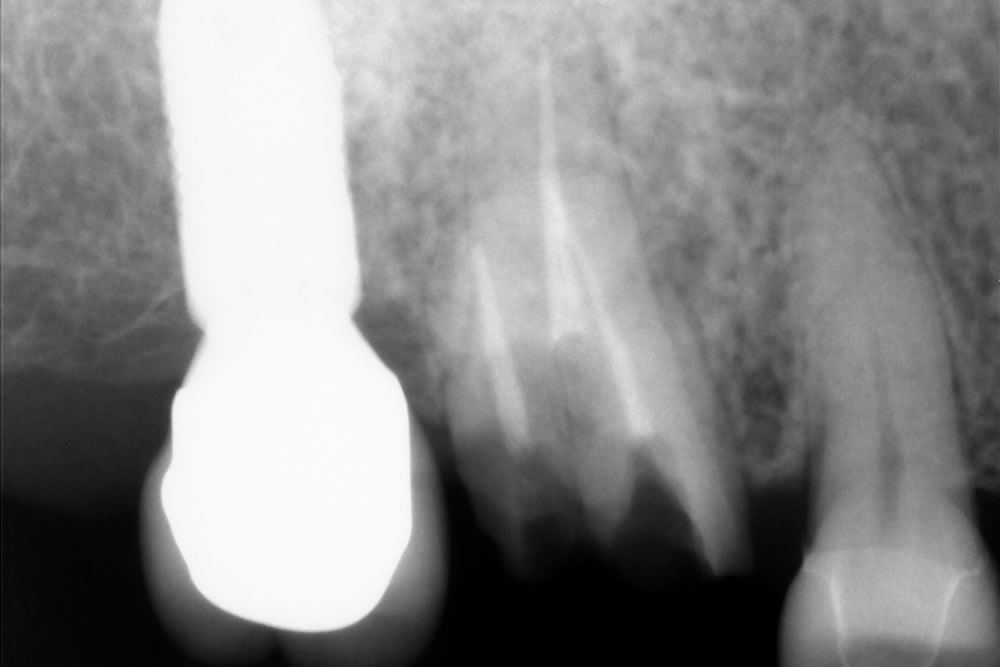

しばらくの間は仮歯で生活していただき、問題がなかったため、仮歯を基に作製した最終上部構造(人工歯)を装着しました。

最終上部構造を装着し、咬み合わせを調整して治療完了となりました。